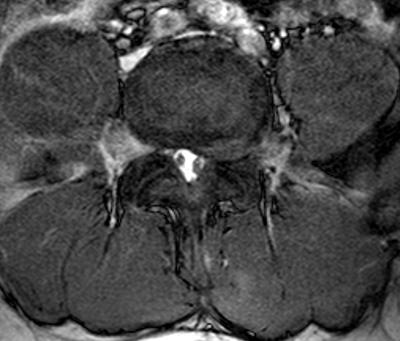

I'm not a qualified radiologist, but I do look at Xrays and scans every day and have done for 35 years. You obviously have a fairly large prolapsed disc at L4-L5, protruding into the foramen, and also compressing the thecal sac.